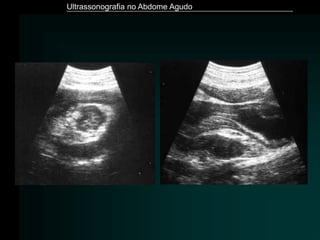

Zwiebel, Elsevier, 5ª ed.: 286

Ultrassonografia no AbdomeAgudo Zwiebel, Elsevier, 5ª ed.: 286